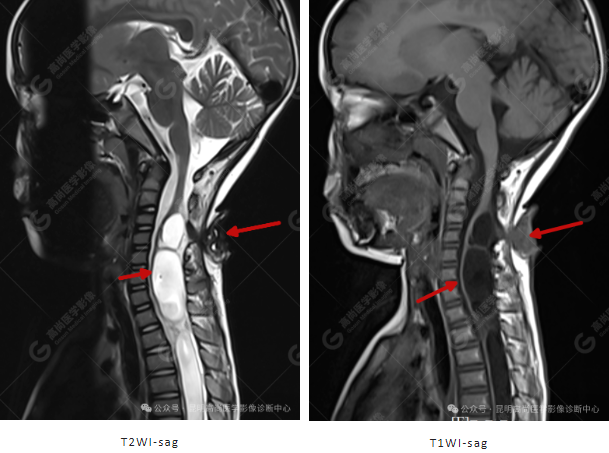

患者女,5 岁,出生时发现颈部包块,大小 3 cm×3 cm,5 年来无变化,拟行手术治疗,要求增强核磁协诊,否认体内金属物,无过敏史。

颈 3-5 层面颈后部软组织不规则片状异常信号影,脊膜膨出可能;颈 3、4 棘突局部显示不清;颈胸髓内(约颈 3-胸 9 椎体水平)异常信号影,考虑囊肿并局部颈髓空洞可能,肿瘤或其他待排;请结合临床及相关检查。